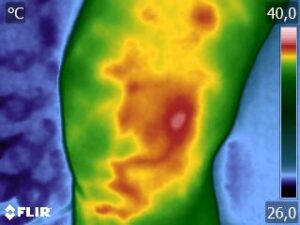

Como no caso da sequência de termogramas abaixo de uma paciente do sexo feminino, 42 anos, sem comorbidade e que apresentou dor em joelhos após treino de musculação. Foi realizado uma Análise Termofuncional e detectado alterações térmicas condizentes com o relato de dor.

Estas informações foram a oportunidade para convencer a paciente a realizar uma ressonância magnética para determinar o grau de comprometimento tecidual. Pois sem isso, após a melhora da dor, a liberação de carga e até a carga terapêutica ficariam limitadas.

Já com este conhecimento foi possível determinar um tratamento que abarcasse as áreas de dor e as áreas de comprometimento tecidual que apresentam inflamação, até a paciente retornar com o resultado da ressonância.

Isso adianta e muito a reabilitação, pois oferece informação que a olho nu não seria possível.